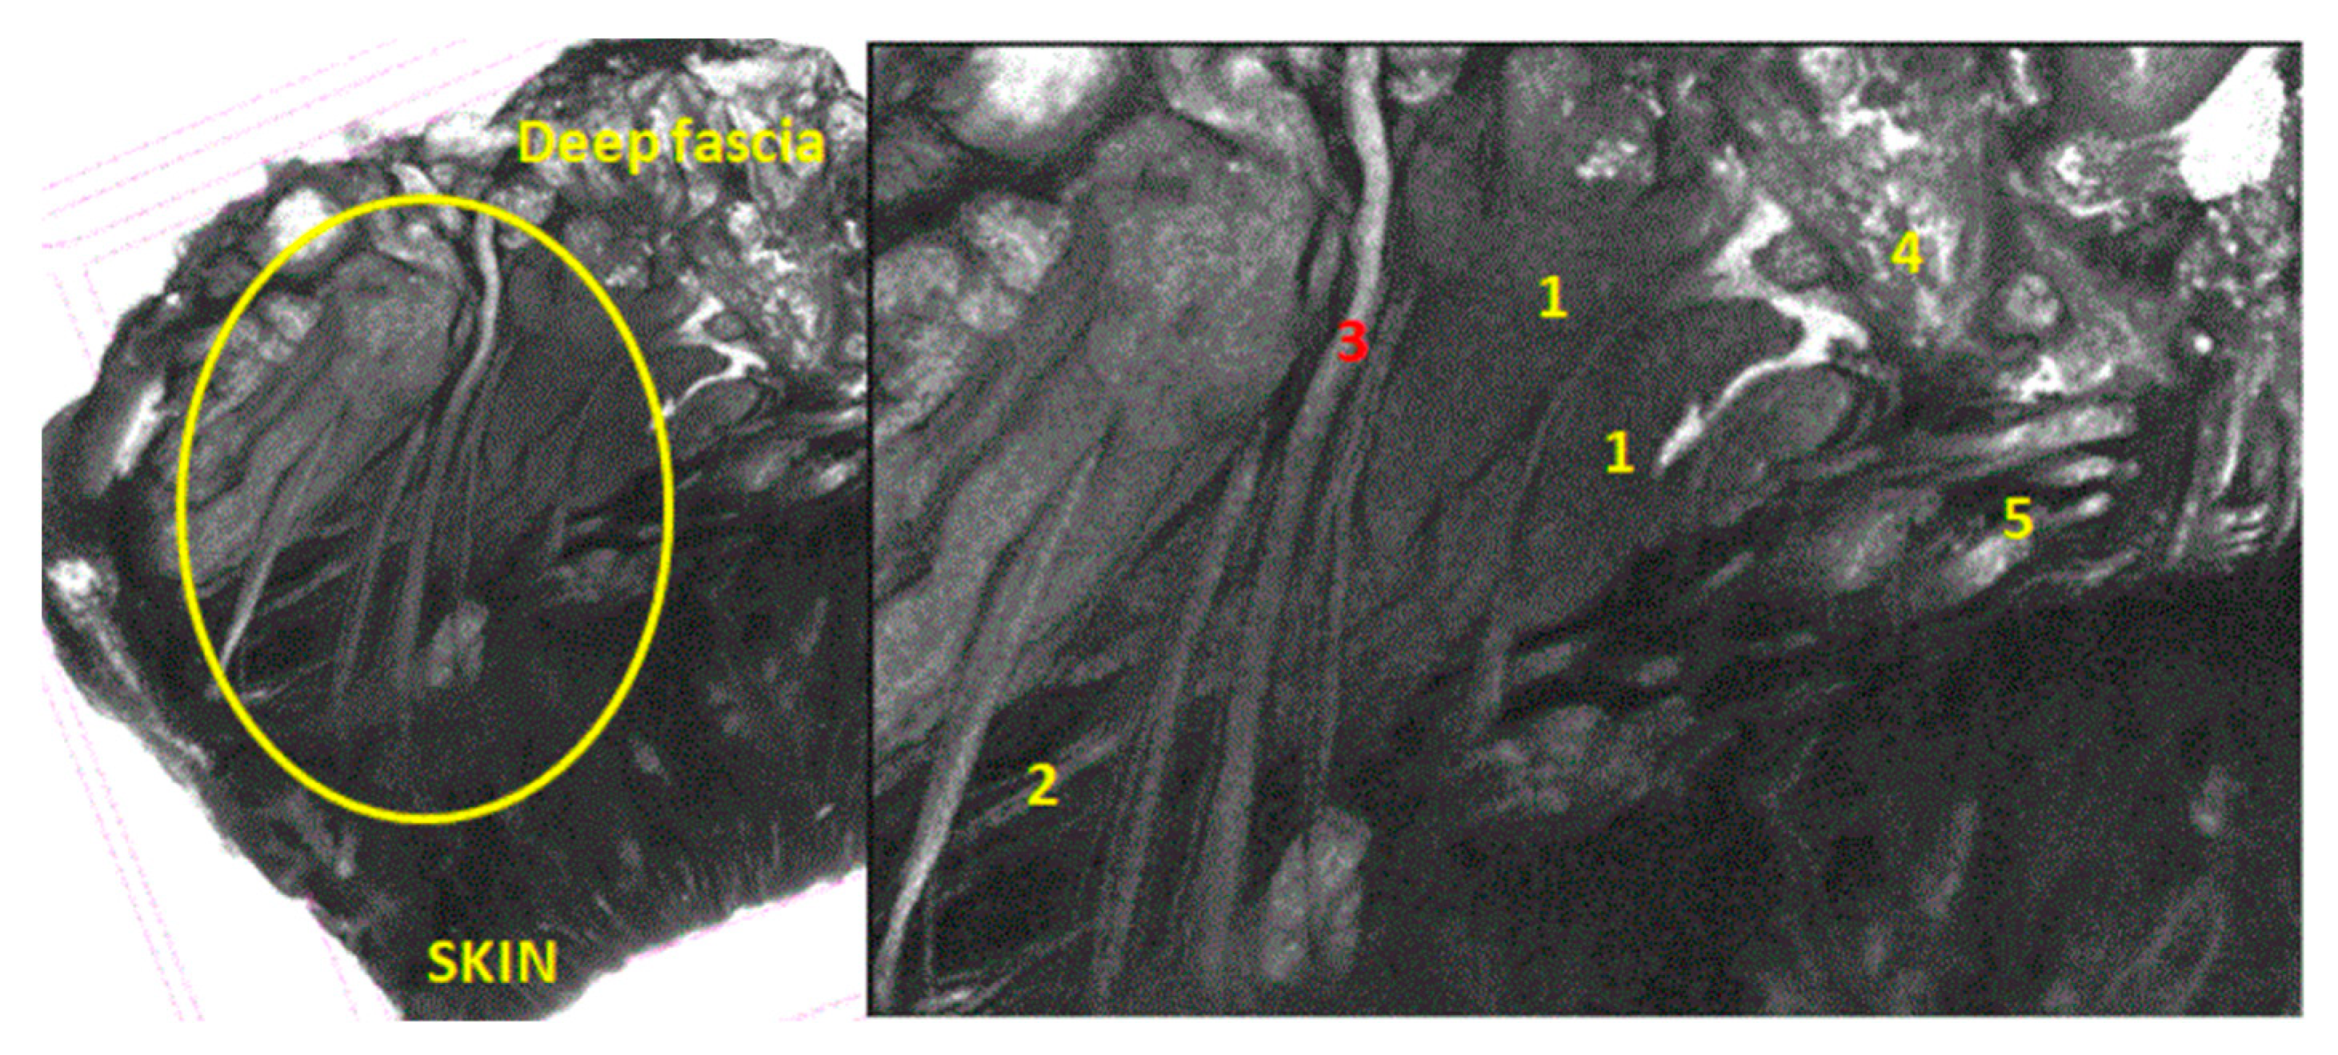

Figure 5. Specimen immersed in Lugol for 7 days from medial side of nasolabial groove; 7 µm scan; yellow circle = SMAS area; 1 = mimic muscles; 2 = fibrous tissue from superficial fascia; 3 = blood vessel; 4 = fat tissue; 5 = attaching manners.

After the first 7 days of immersion in the Lugol solution, the scan results showed a distinctive vascular pathway through the muscles, medially to the nasolabial fold. The blood vessel was followed by nervous fibers (Figure 5).

Figure 6. Specimen immersed in Lugol for 7 days from nasal pyramid area; 1 = mimic muscle (procerus); 2 = sub-SMAS fat tissue; 3 = superficial fascia, 4 = blood vessels; ML = muscle layer; CL = conjunctive layer; SPL = superficial fascia layer; whole green rectangular = SMAS.

On the 20 µm scan after 7 days of immersion, we were able to distinguish an entire network of blood vessels within the thickness of the SMAS in the area of the nasal pyramid (Figure 6). They cross the SMAS in a random manner—sagittally, coronary, or tortuously. There are no particular conjunctival tissue fibers that follow the blood vessels in this study. Sagittal vessels split in a “T” shape manner when they reach the skin. Therefore, they form a clearly distinguishable blood distribution system in parallel with the skin.

At the same time, we observed a mixed type of blood vessels in this area; cutaneous thick branches cross the SMAS and deep, thinner branches run within its thickness.